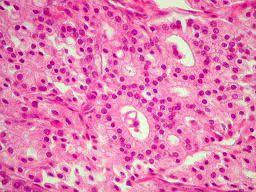

BIÓPSIAS DE MAMA

– PAAF (punção aspirativa por agulha fina)

– Core-Biópsia guiada por ultrassom